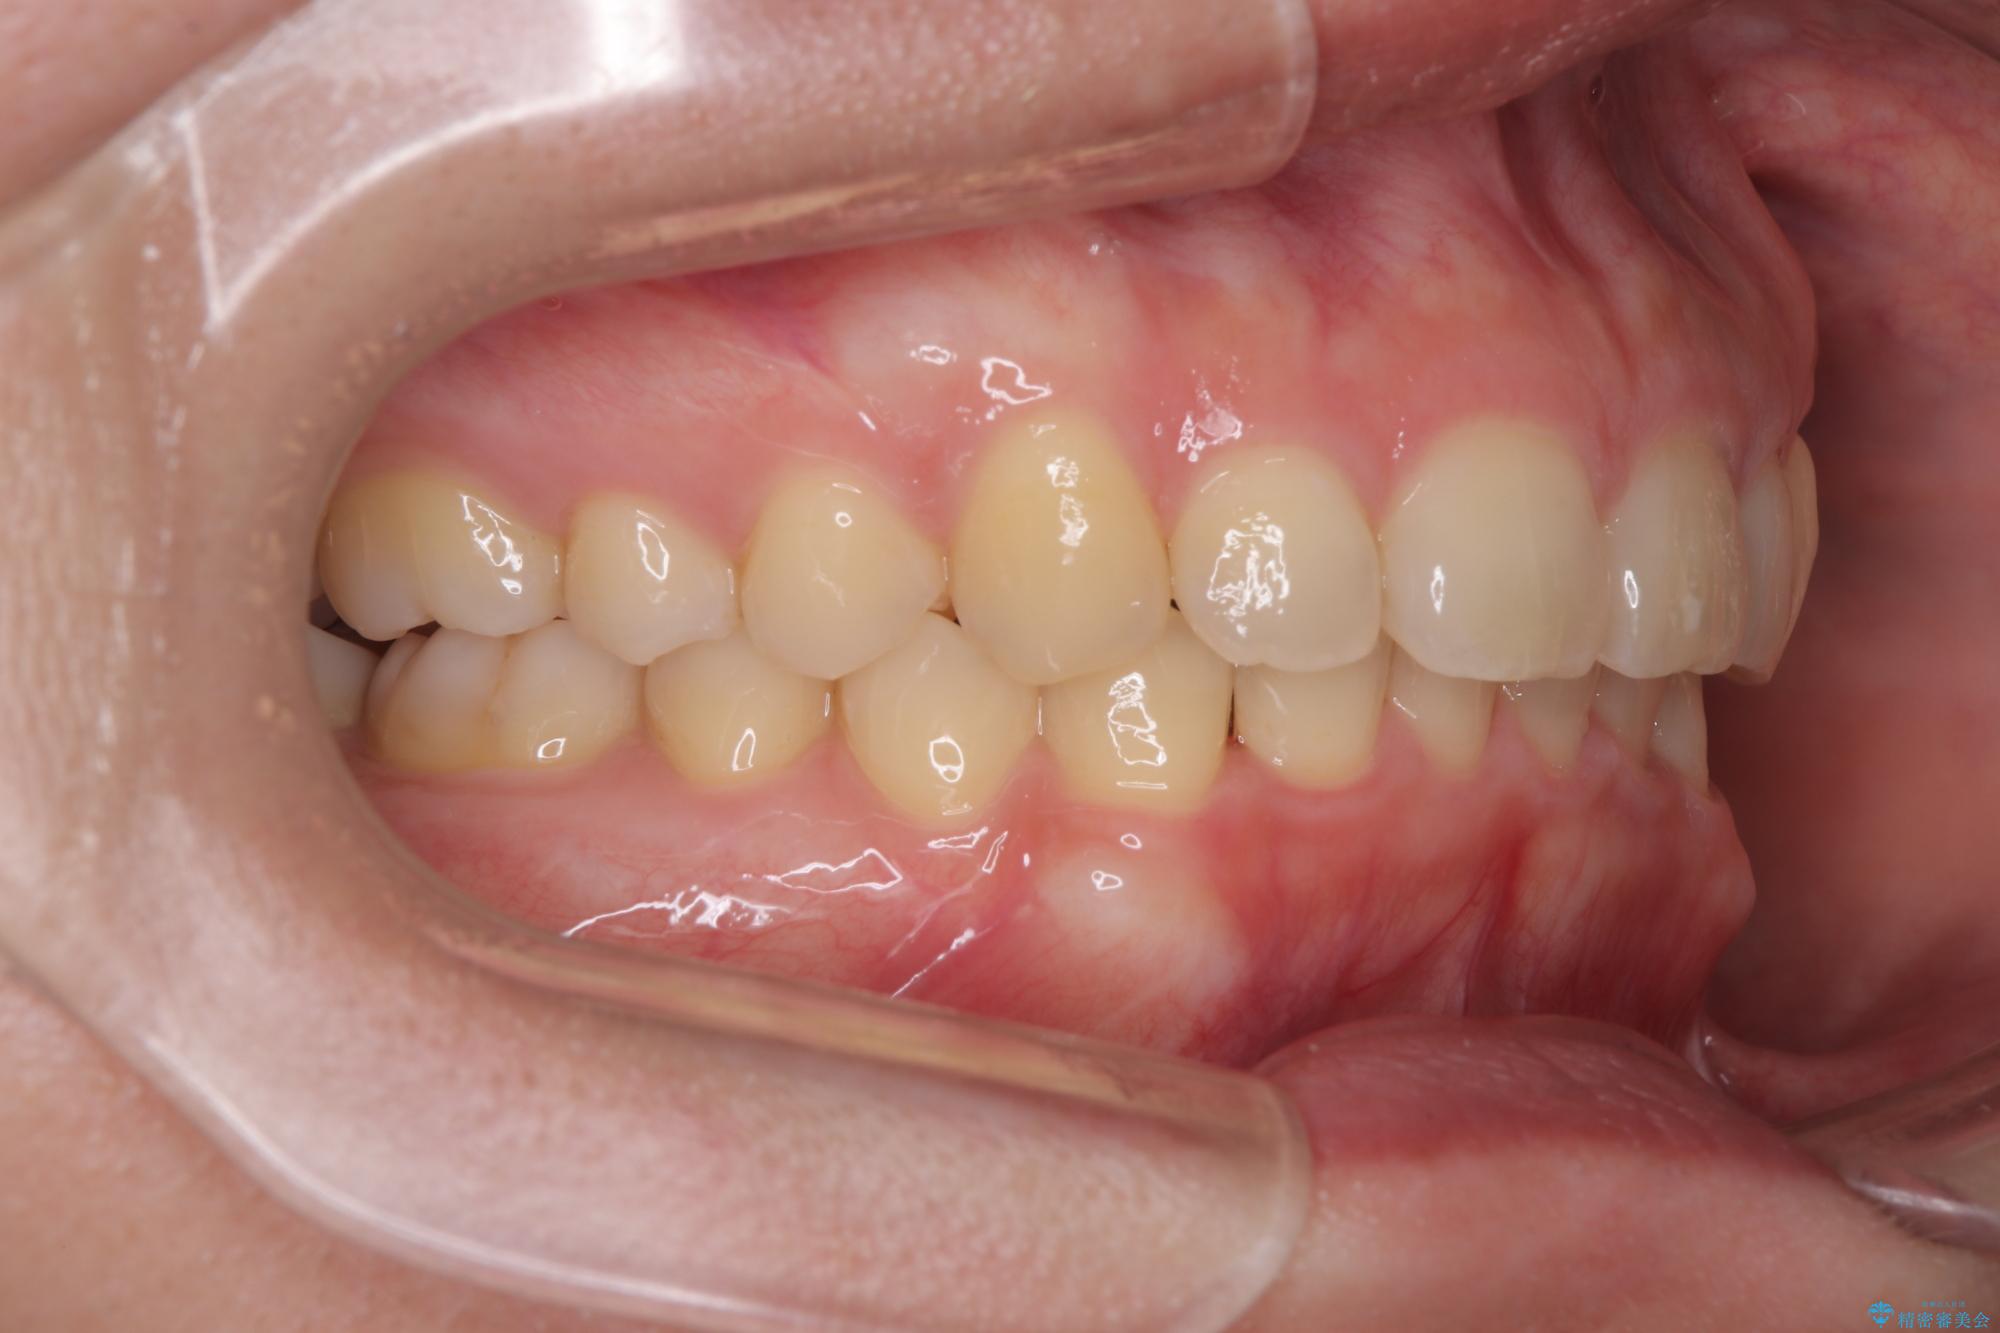

下顎臼歯を起き上がらせるためにユーティリティーアーチを使用し、一気に深い咬み合わせを改善することができました。